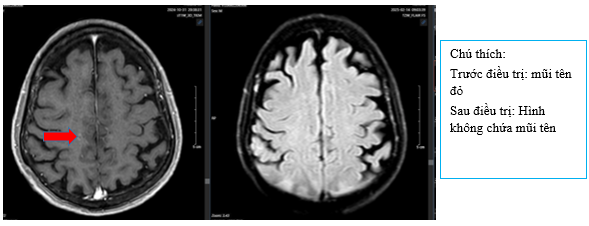

+ Chụp MRI sọ não sau điều trị:

Hình 8: So sánh phi chụp cộng hưởng từ sọ não trước điều trị có nốt tăng ngấm thuốc sau tiêm vùng vỏ não thùy trán thùy đỉnh phải ~ 3mm (mũi tên đỏ) của phim chụp trước điều trị. Hiện tại chụp lại phim MRI não đã không còn phát hiện các nốt ngấm thuốc bất thường.